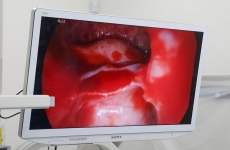

Innowacyjny zabieg udrożnienia zatok w Medical Clinic Podhale